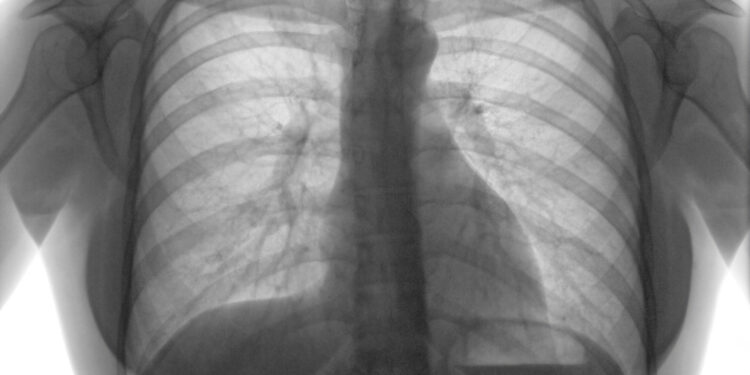

De acordo com a enfermeira coordenadora do Programa Municipal de Tuberculose, Marlene Terezinha Boreck, a Tuberculose é uma doença infecciosa que atinge principalmente os pulmões, mas também pode ocorrer nos gânglios, rins, ossos, meninges e outros locais do organismo. “A nossa intenção enquanto profissionais da saúde é a divulgação e sensibilização sobre os principais sinais e sintomas da doença, para que casos sejam captados precocemente e também desmistificar pré conceitos relacionados a ela”, afirma.